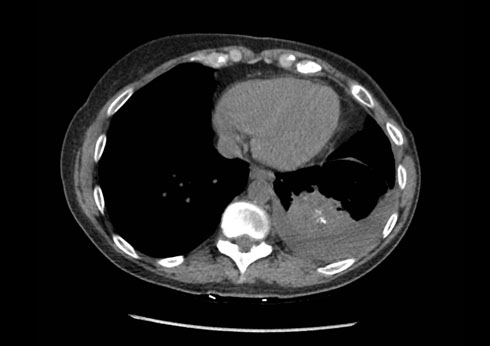

The patient started T-DM1 189 mg intravenously on day one of a 21 day cycle. A repeat chest CT two months after initiation of therapy demonstrated response with a decrease in the size of the left lower lung mass to 5.2 cm in diameter, representing a 32% reduction in size (Figure 1). This was also associated with a decrease in the size and number of additional pulmonary nodules. She tolerated the therapy February to August 2018 without disease progression. She experienced myelosuppression with severe thrombocytopenia evidenced by an undetectable white blood cell count and ultimately required a dose adjustment of the therapy.

Figure 1: A repeat chest CT two months after initiation of therapy demonstrated response with a decrease in the size of the left lower lung mass to 5.2 cm in diameter.